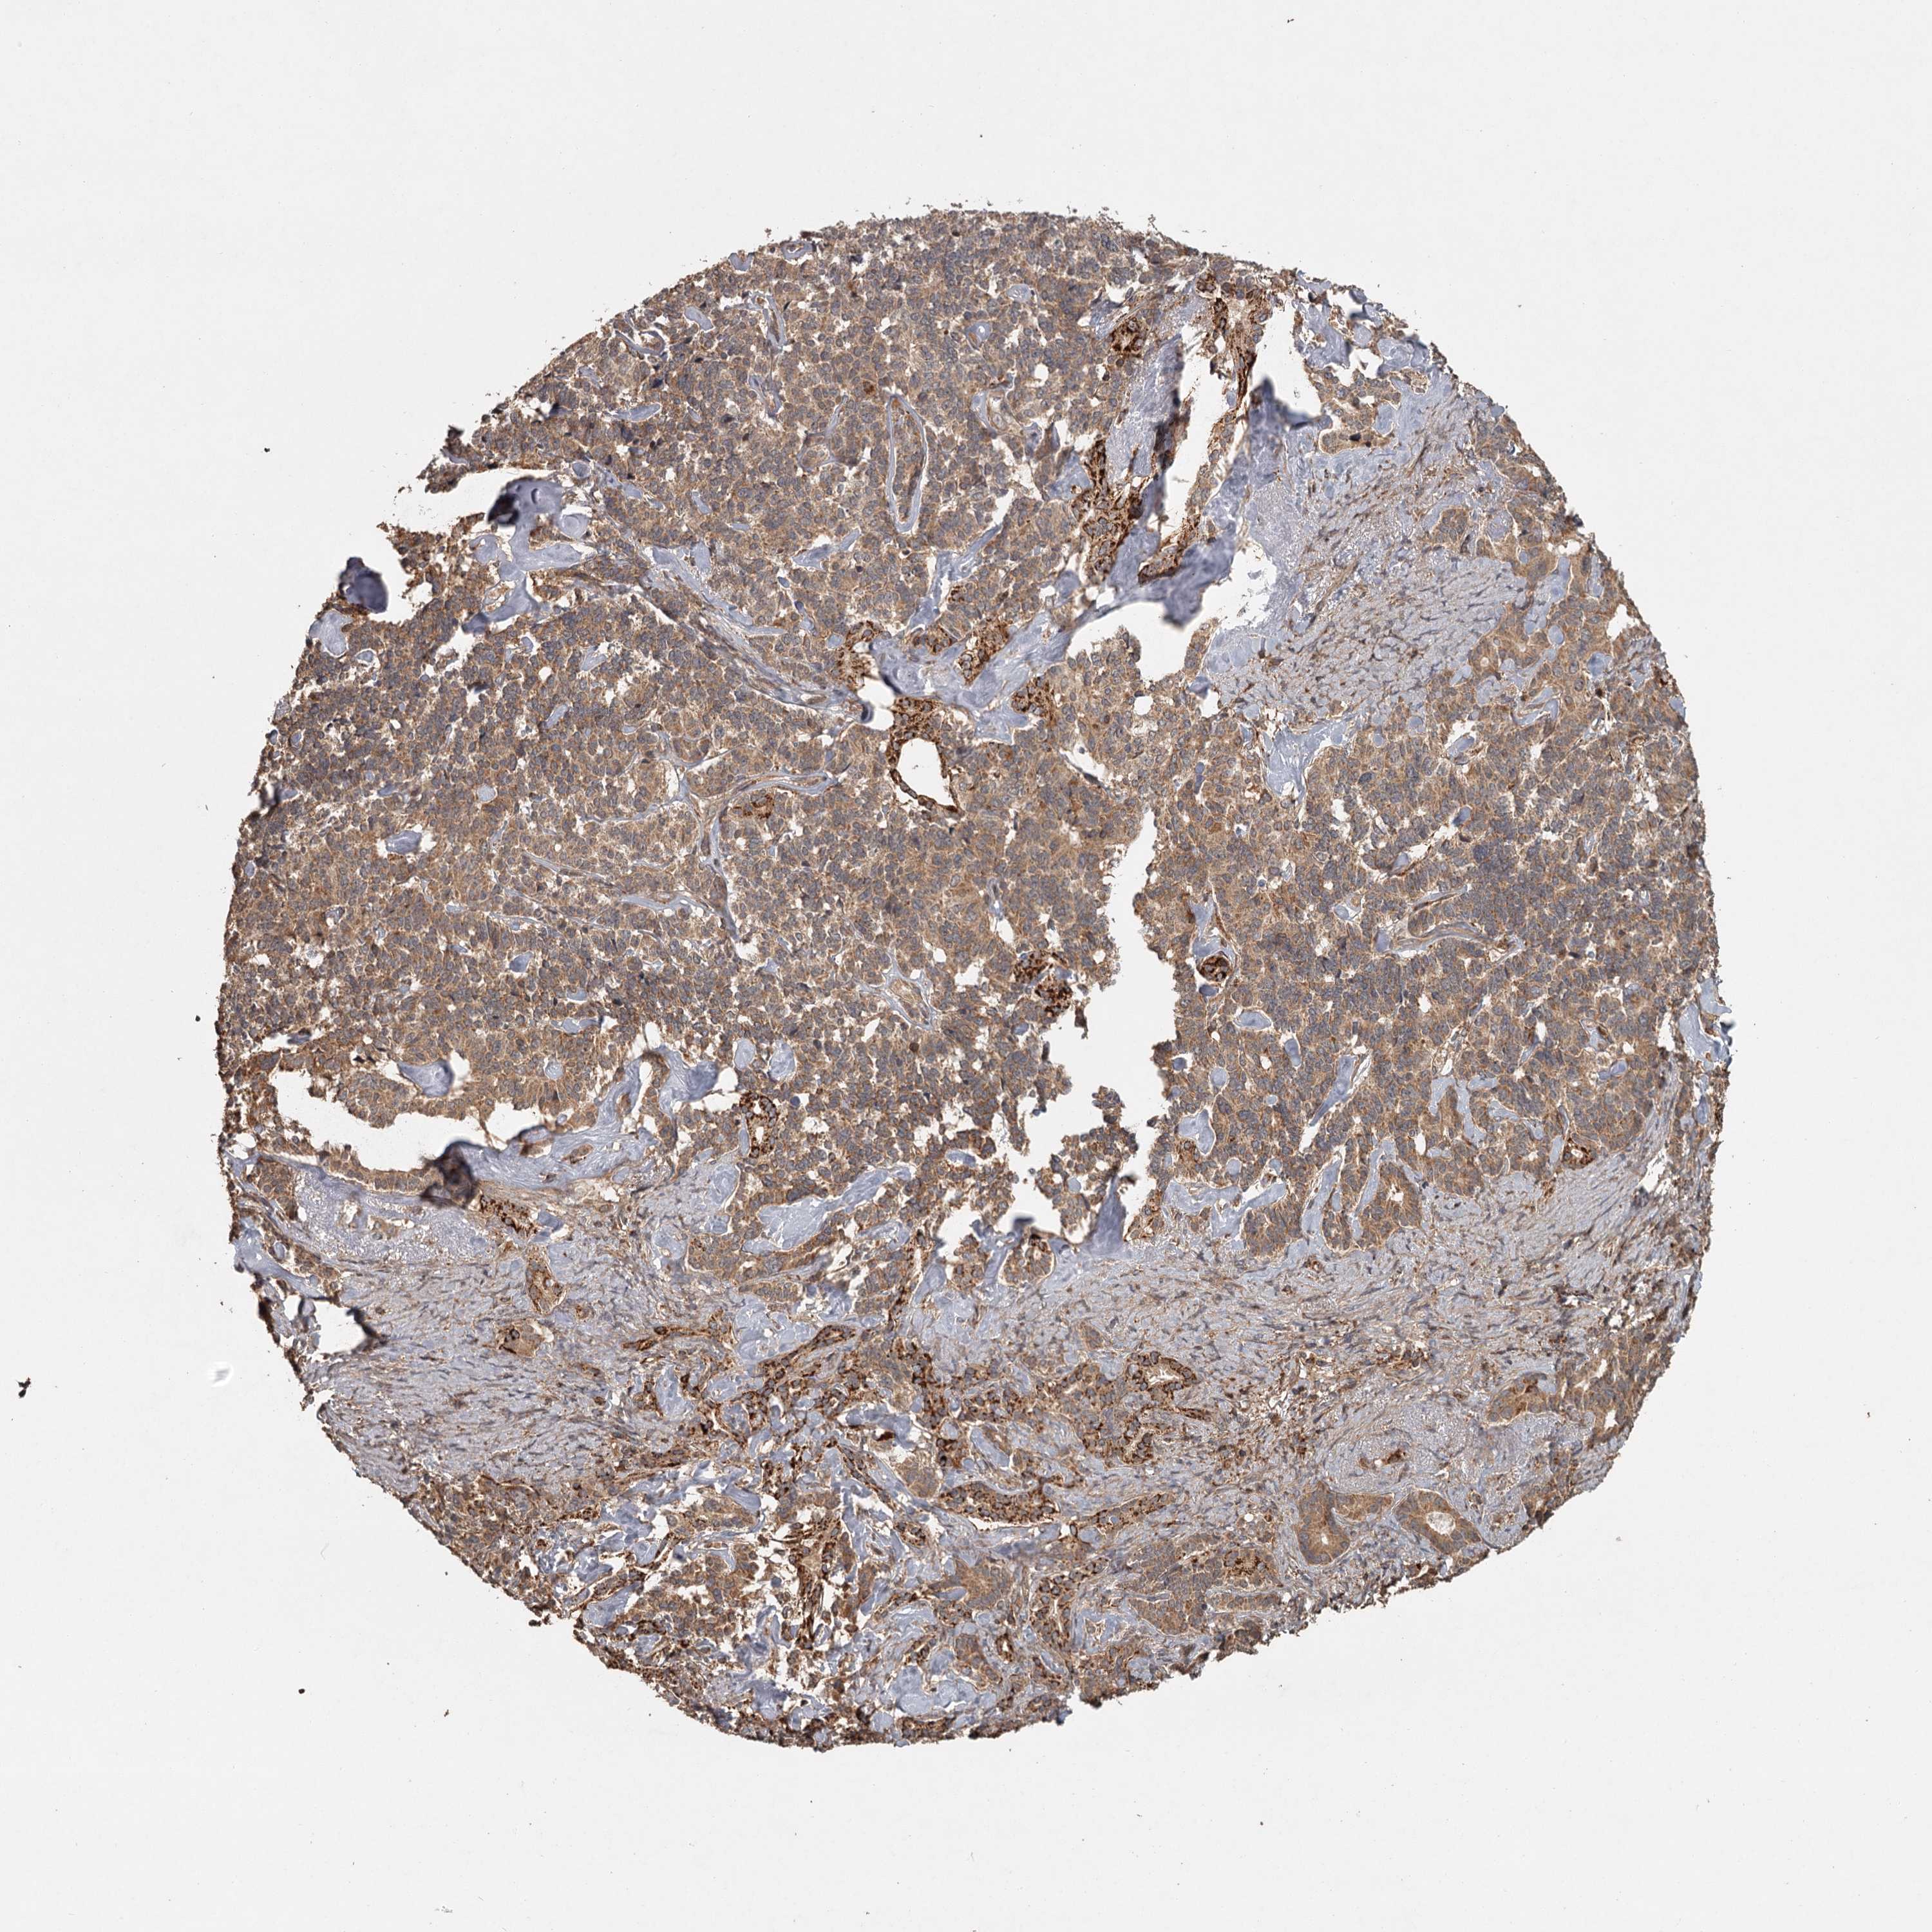

PANCREATIC CANCER - Protein expressioni

A mouse-over function shows sample information and annotation data. Click on an image to view it in a full screen mode. Samples can be filtered based on level of antibody staining by selecting one or several of the following categories: high, medium, low and not detected. The assay and annotation is described here.

Note that samples used for immunohistochemistry by the Human Protein Atlas do not correspond to samples in the TCGA dataset.

Antibody stainingi

Antibody staining in the annotated cell types in the current human tissue is reported as not detected, low, medium, or high, based on conventional immunohistochemistry profiling in selected tissues. This score is based on the combination of the staining intensity and fraction of stained cells.

Each image is clickable and will lead to virtual microscopy that enables deeper exploration of all samples and also displays staining intensity scores, fraction scores and subcellular localization as well as patient and tissue information for each sample.

Antibody HPA039106

Staining

High

Medium

Low

Not detected

Intensity

Strong

Moderate

Weak

Negative

Quantity

>75%

75%-25%

<25%

None

Location

Nuclear

Cytoplasmic/membranous

Cytoplasmic/membranous,nuclear

Adenocarcinoma, NOS